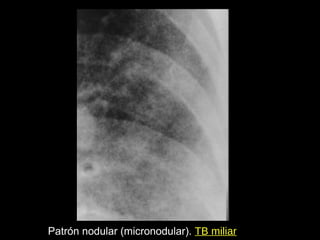

Patrón nodular (micronodular). TB miliar

Nódulos finos. TBC diseminada